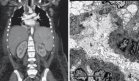

El estudio histopatológico confirmó un tumor de células gigantes grado II con proliferación neoplásica de células estromales mononucleares, bajo recuento mitótico y presencia de células gigantes multinucleadas. La inmunotinción fue positiva para Ki-67 (5%), CD68 y vimentina. A los seis meses, la paciente recuperó la movilidad y sensibilidad en miembros inferiores.